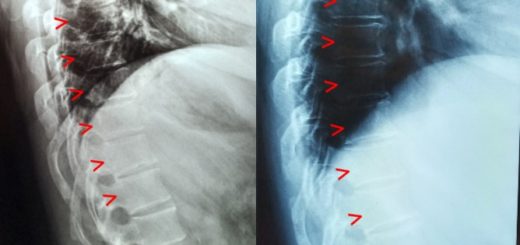

Shortness of Breath due to Hunching (Hyperkyphosis)